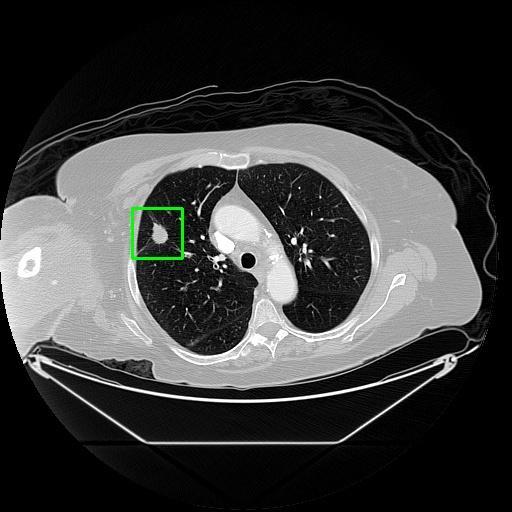

We developed an AI-based system using deep learning models for analyzing lung CT scans to detect and classify pulmonary nodules. We chose the YOLOv11 architecture for its enhanced object detection capability and adapted it specifically for medical imaging, incorporating pixel-level precision and severity classification.

Classification into three severity levels with colored bounding boxes.

Designed a severity classification system that categorizes nodules into null, moderate, and severe using colored bounding boxes, assisting in rapid clinical decision-making.